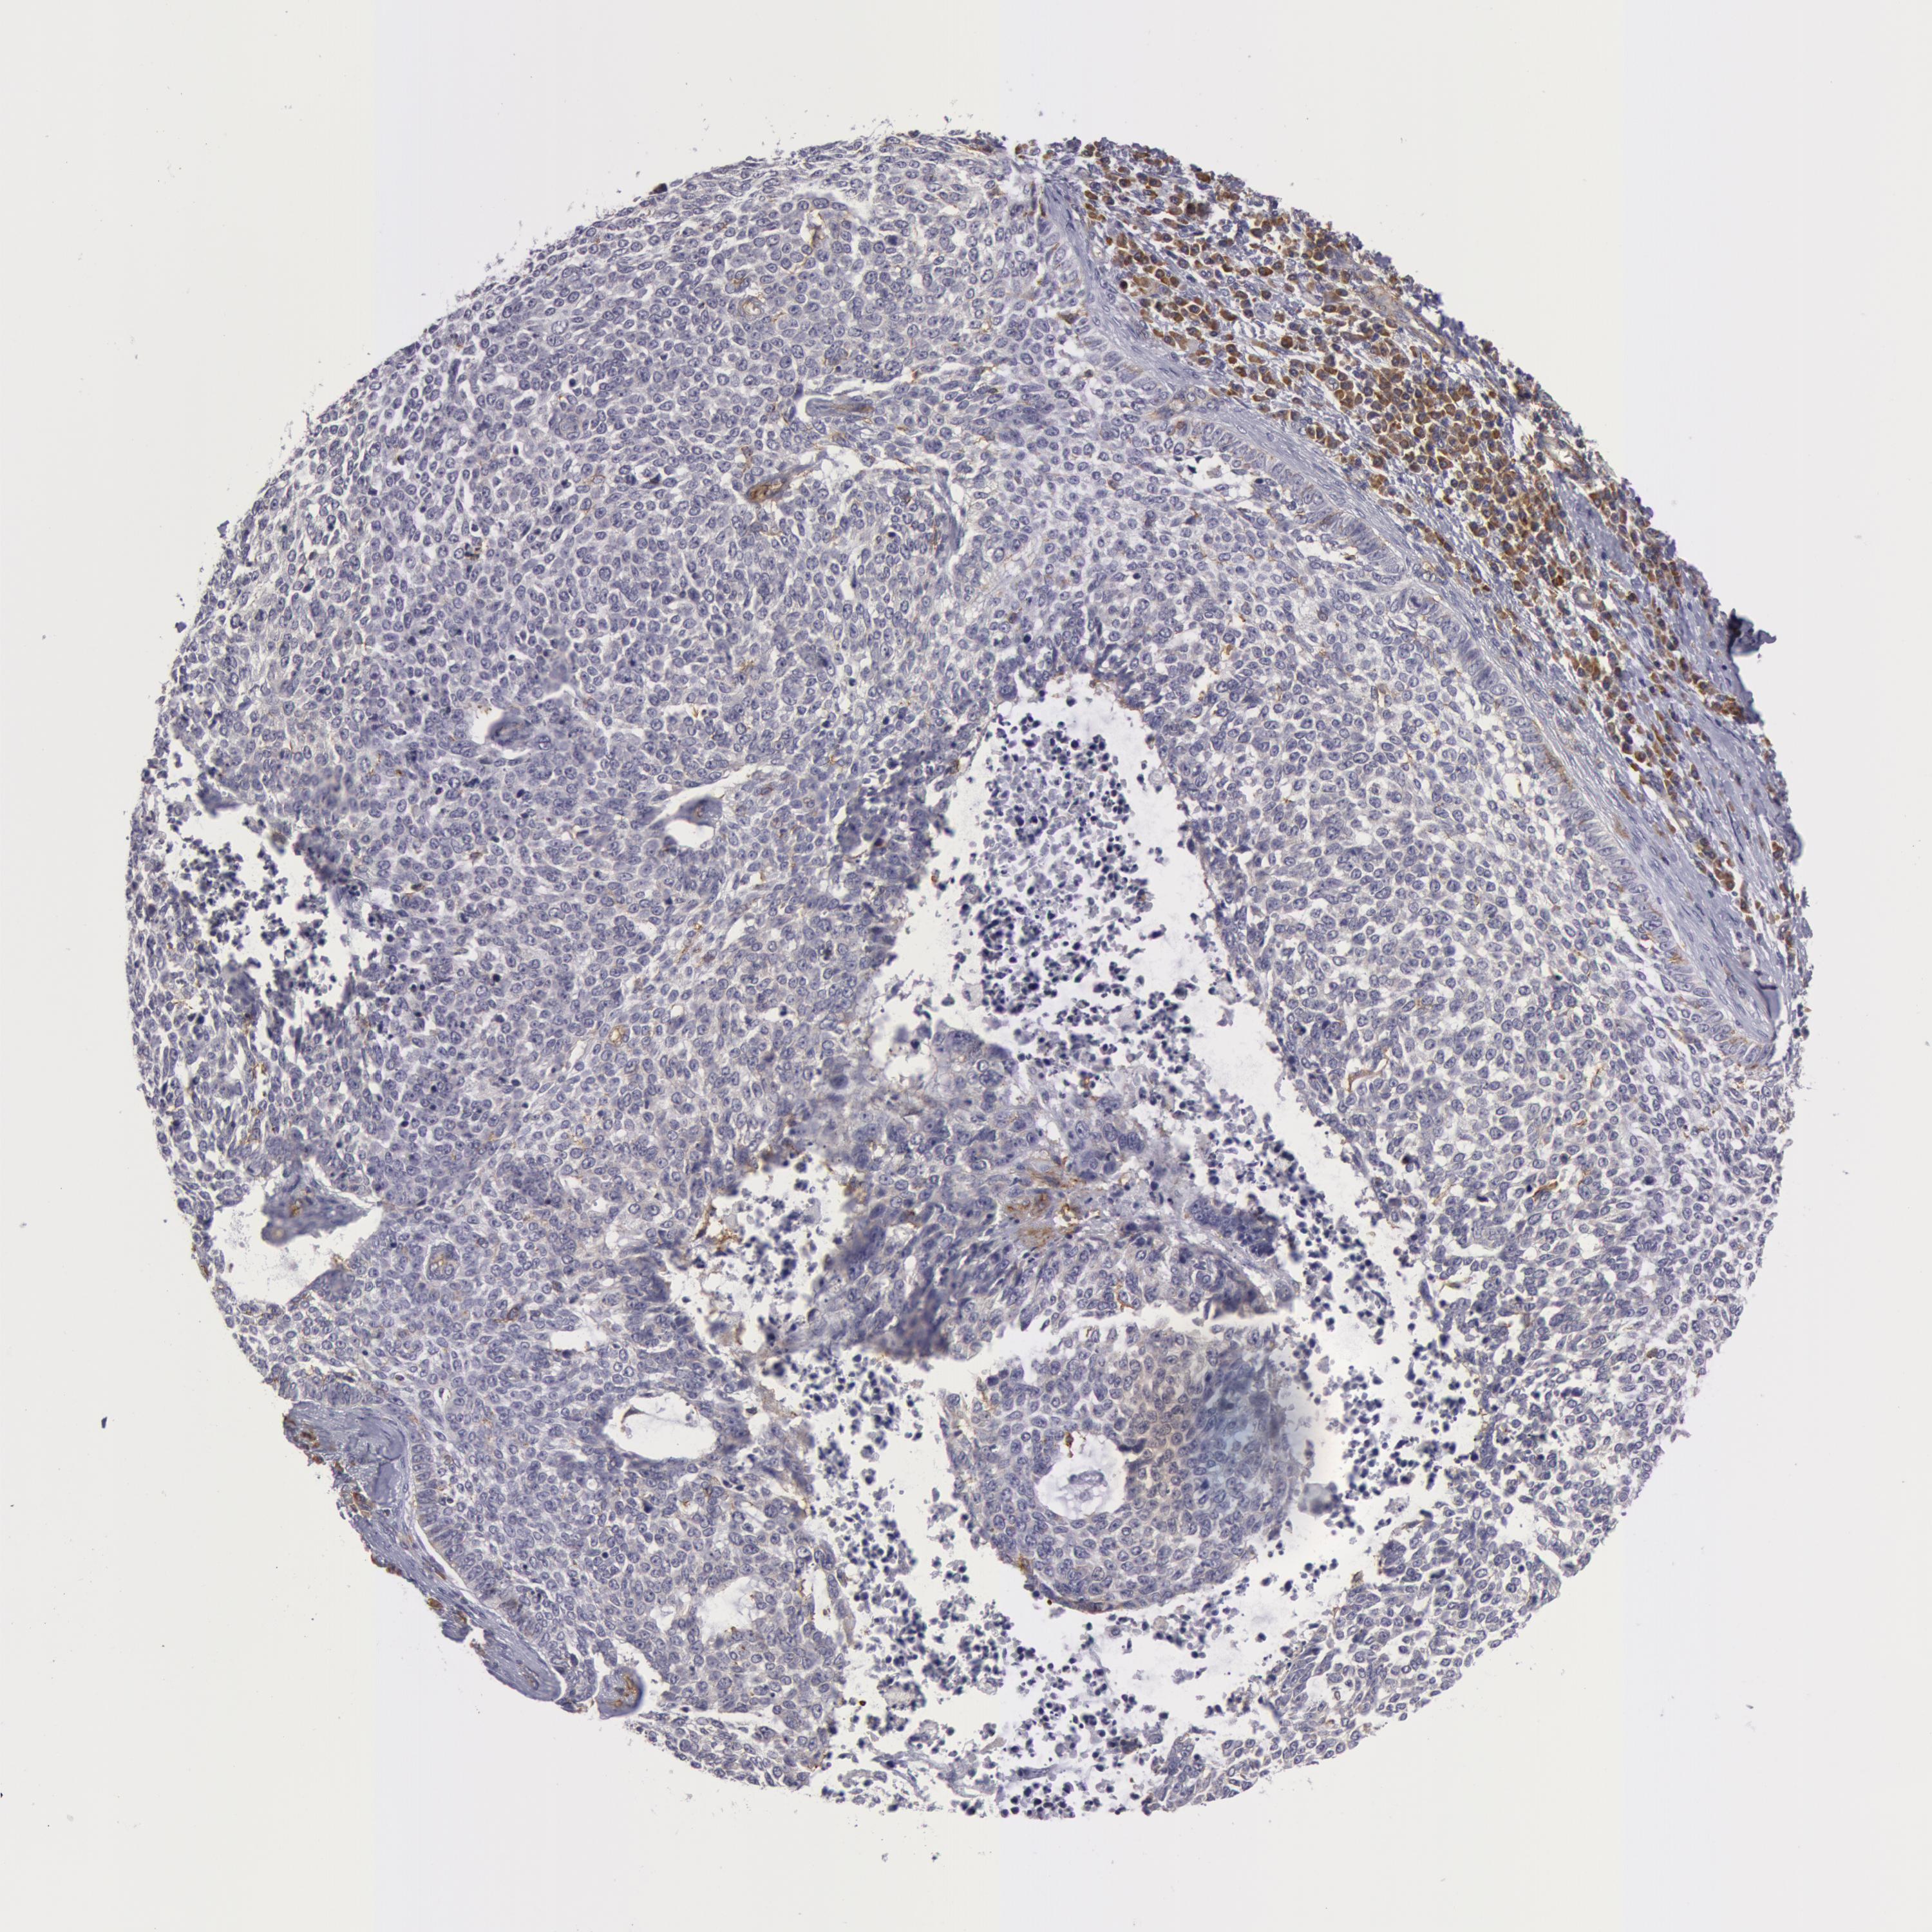

SKIN CANCER - Protein expressioni

A mouse-over function shows sample information and annotation data. Click on an image to view it in a full screen mode. Samples can be filtered based on level of antibody staining by selecting one or several of the following categories: high, medium, low and not detected. The assay and annotation is described here.

Antibody stainingi

Antibody staining in the annotated cell types in the current human tissue is reported as not detected, low, medium, or high, based on conventional immunohistochemistry profiling in selected tissues. This score is based on the combination of the staining intensity and fraction of stained cells.

Each image is clickable and will lead to virtual microscopy that enables deeper exploration of all samples and also displays staining intensity scores, fraction scores and subcellular localization as well as patient and tissue information for each sample.

Antibody HPA001554

Staining

High

Medium

Low

Not detected

Intensity

Strong

Moderate

Weak

Negative

Quantity

>75%

75%-25%

<25%

None

Location

Nuclear

Cytoplasmic/membranous

Cytoplasmic/membranous,nuclear

Squamous cell carcinoma, NOS

Basal cell carcinoma